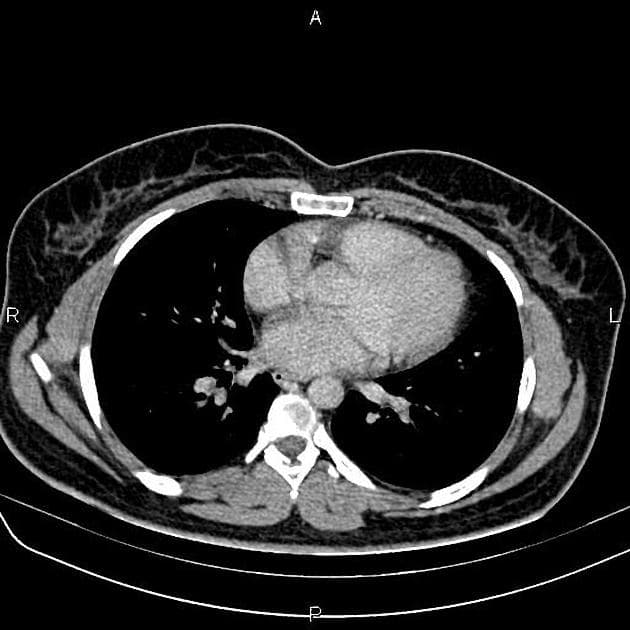

- Tổn thương lớn nhất nằm ở thuỳ trái gan, phân đoạn 3, có tín hiệu đồng tín hiệu (isointense) so với nhu mô gan trên hình ảnh cộng hưởng từ (MRI) trọng T1 và không giảm tín hiệu trên hình ảnh out-of-phase, điều này không gợi ý có sự hiện diện của mỡ.

- Trên hình ảnh trọng T2, tổn thương có tín hiệu đồng tín hiệu đến hơi tăng tín hiệu so với gan, với vùng trung tâm tăng tín hiệu, phù hợp với sẹo trung tâm.

- Tổn thương cho thấy tăng quang động mạch, trong đó vùng sẹo trung tâm không tăng quang, nhưng đến thì muộn thì sẹo trung tâm xuất hiện tăng quang chậm.

Nhiều tổn thương tăng sản khu trú dạng nốt (FNH) có thể xuất hiện trong hội chứng FNH nhiều ổ (multiple FNH syndrome) hoặc bệnh di truyền giãn mạch máu dạng telangiectasia xuất huyết (hereditary hemorrhagic telangiectasia).

Tăng sản khu trú dạng nốt (FNH) là tổn thương gan lành tính, thường gặp ở phụ nữ trẻ đến trung niên, thường được phát hiện tình cờ khi chụp hình. Tổn thương đặc trưng bởi sẹo trung tâm với các vách xơ tỏa ra và cấu trúc mạch máu bất thường. Trên MRI, FNH có tín hiệu đồng tín hiệu ở T1, hơi tăng tín hiệu ở T2, tăng quang mạnh ở thì động mạch và tăng quang chậm ở sẹo trung tâm ở thì muộn. Nhiều ổ FNH có thể xuất hiện đơn độc hoặc trong hội chứng FNH nhiều ổ hoặc bệnh di truyền giãn mạch máu dạng telangiectasia xuất huyết (HHT), bệnh này liên quan đến các dị dạng mạch máu ở cơ quan khác. Việc phân biệt với u tuyến tế bào gan rất quan trọng vì u tuyến có nguy cơ xuất huyết và ác tính hóa. Việc không có mỡ, có sẹo trung tâm và kiểu tăng quang đặc trưng giúp nghi ngờ FNH. Sinh thiết hiếm khi cần thiết nếu hình ảnh điển hình.